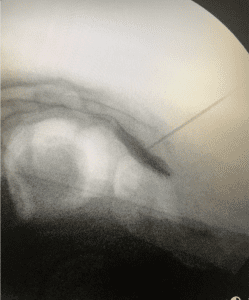

El siguiente paso para mejorar los síntomas en pacientes con coccigodinea es la radiofrecuencia del ganglio impar también llamado de Walther. Técnica descrita en 1990. Su ubicación anatómica es en la zona anterior de la articulación sacrococcigea, aunque existen variantes anatómicas según el tipo de dolor.

Procedimiento de radiofrecuencia aplicado en el ganglio impar para tratamiento de dolor crónico

Con esta técnica lo que se consigue es una mejoría mas duradera en el tiempo, que puede ser de hasta 2 años. Se atraviesa el ligamento con la aguja de radiofrecuencia o un trocar y se comprueba la localización con el contraste que debe dibujar el plexo en posición lateral. Tras el procedimiento se infiltra con anestésico y corticoides.